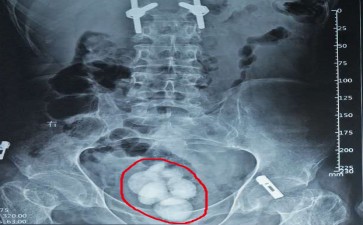

在人体的泌尿 “储运系统” 中,膀胱就像一个弹性十足的 “尿液暂存仓库”,白天收集肾脏送来的尿液,等达到一定量就发出 “排泄信号”。可当膀胱结石出现,就像仓库里莫名攒起了 “坚硬杂物”,不仅占地方,还会搅得整个仓库不得安宁。

这些 “坚硬杂物” 的出现,和仓库的 “使用习惯” 密切相关。肾脏或输尿管的结石 “掉落” 进来,如同其他地方的碎石滚进了仓库;长期憋尿让尿液在仓库里 “久存变质”,水分被过度吸收,杂质慢慢凝结成块;前列腺增生导致尿液排出不畅,好比仓库出口被堵住,残留的尿液成了结石滋生的 “温床”。起初,小结石可能只是在仓库里 “安静待着”,让人没啥感觉;可随着它们变大,排尿时就会出现刺痛,像仓库里的杂物硌到了内壁,严重时还会造成梗阻,让尿液排不干净,进而引发感染,出现尿频、尿急等 “仓库警报”。